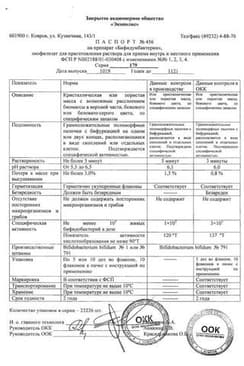

Бифидумбактерин лиофилизат для приготовления раствора для приема внутрь и местного применения флакон 5доз фл.10 шт

Общие характеристики

Состав препарата Бифидумбактерин

Лиофилизат для приготовления раствора для приема внутрь и местного применения1 фл.

Bifidobacterium bifidum 5 доз

5 доз - флаконы (10) - пачки картонные.